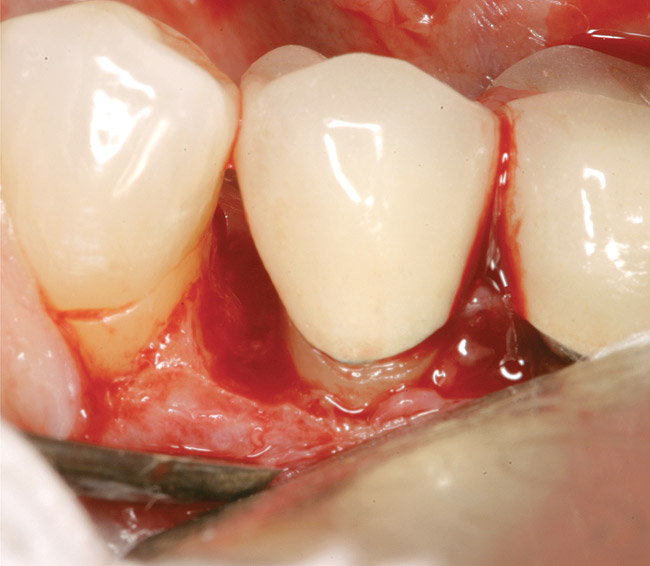

In this example, the more predictable option would have been to place an implant in the No. 30 position and restore the area as three single units. However, the treatment delivered involved a four-unit fixed bridge, which then included tooth No. 28. Unfortunately, this bridge failed at approximately 5 years (Figure 7 and Figure 8) because of a root fracture of tooth No. 29 and advanced furcation involvement with residual endodontic infection of tooth No. 30. The inclusion of tooth No. 28 into the bridge also decreased its long-term prognosis because of its preparation.43 The alternative restorative option of a RPD also would decrease the prognosis of the RPD abutment teeth, which fail more often than FPD abutment teeth.43

Figure 7  Condition of the teeth seen in Figure 6, approximately 5 years after restoration. Note the extensive furcation involvement of tooth No. 31 and its residual periapical radiolucency.

Figure 7

Figure 8  Same case as in Figure 7 showing teeth Nos. 28 and 29. Note that tooth No. 28 was included into the four-unit restoration, and the small radiolucency on the distal tooth No. 29, which was associated with a root fracture.

Figure 8